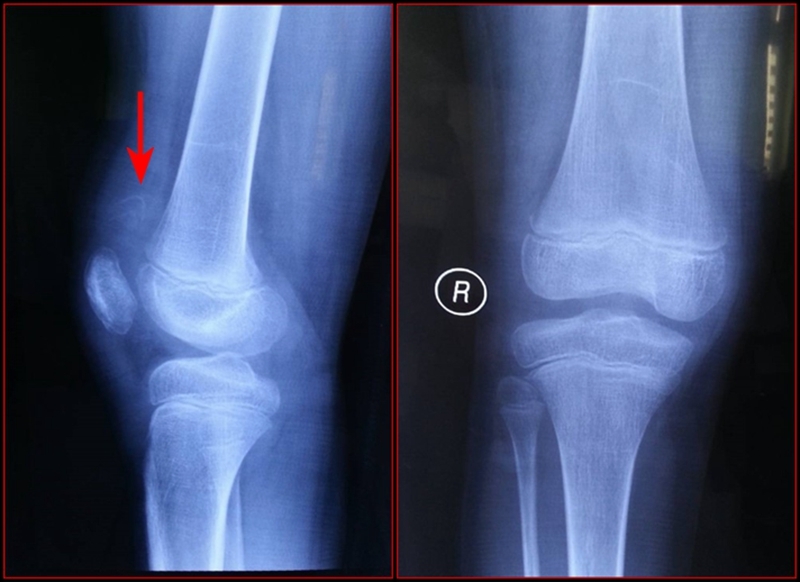

图2 受伤3周X线片

考虑此患儿伤后已3周,组织全科讨论,确定诊断为:髌骨上极陈旧性套状撕脱骨折。充分与家属沟通远期预后。